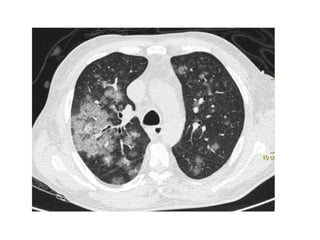

Multiple calcific densities in both lungs with thickening and increased density

along the fissure and along the mediastinal margin , a black pleural line is

noted